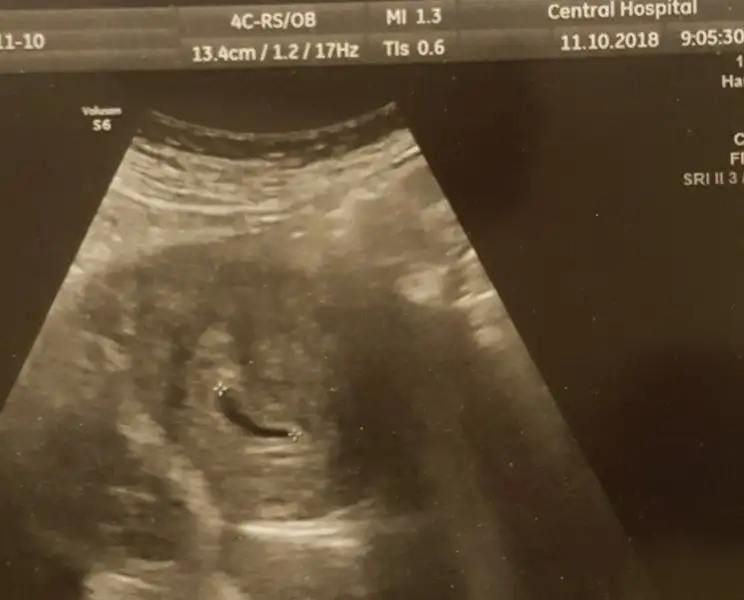

5+6 günlükken gördüm canım.Feeling07 canım sen keseyi kaç günlükken ogrendin